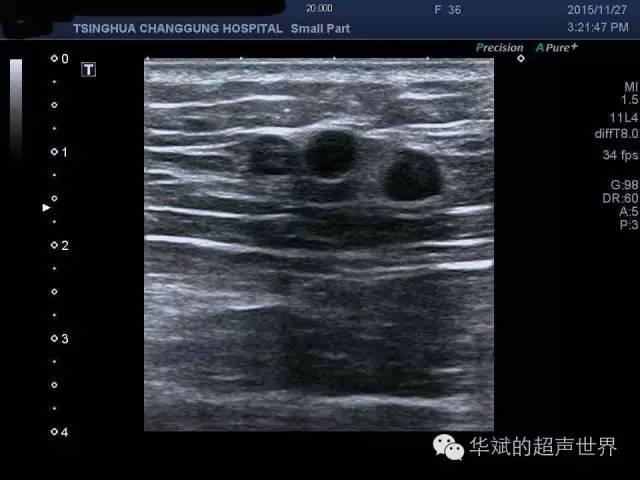

超声可见双侧臀部脂肪层内多发圆形无回声结节,边界清晰,后方无回声增强,具有典型的积油囊肿的特点。